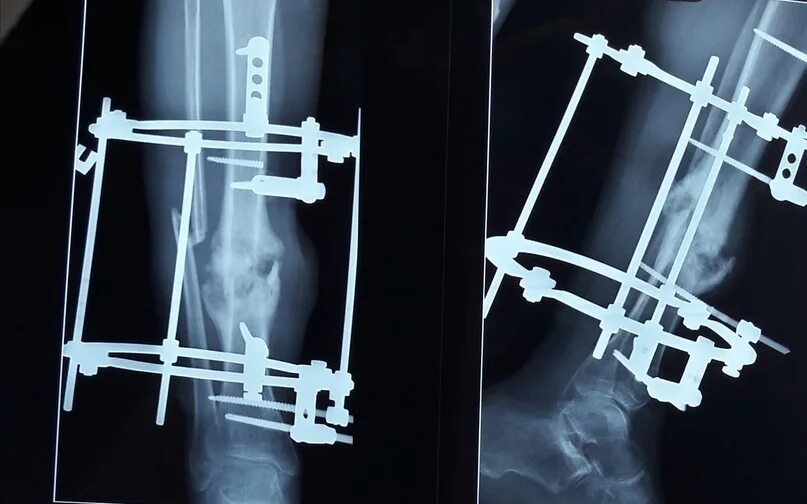

Остеосинтез мрт